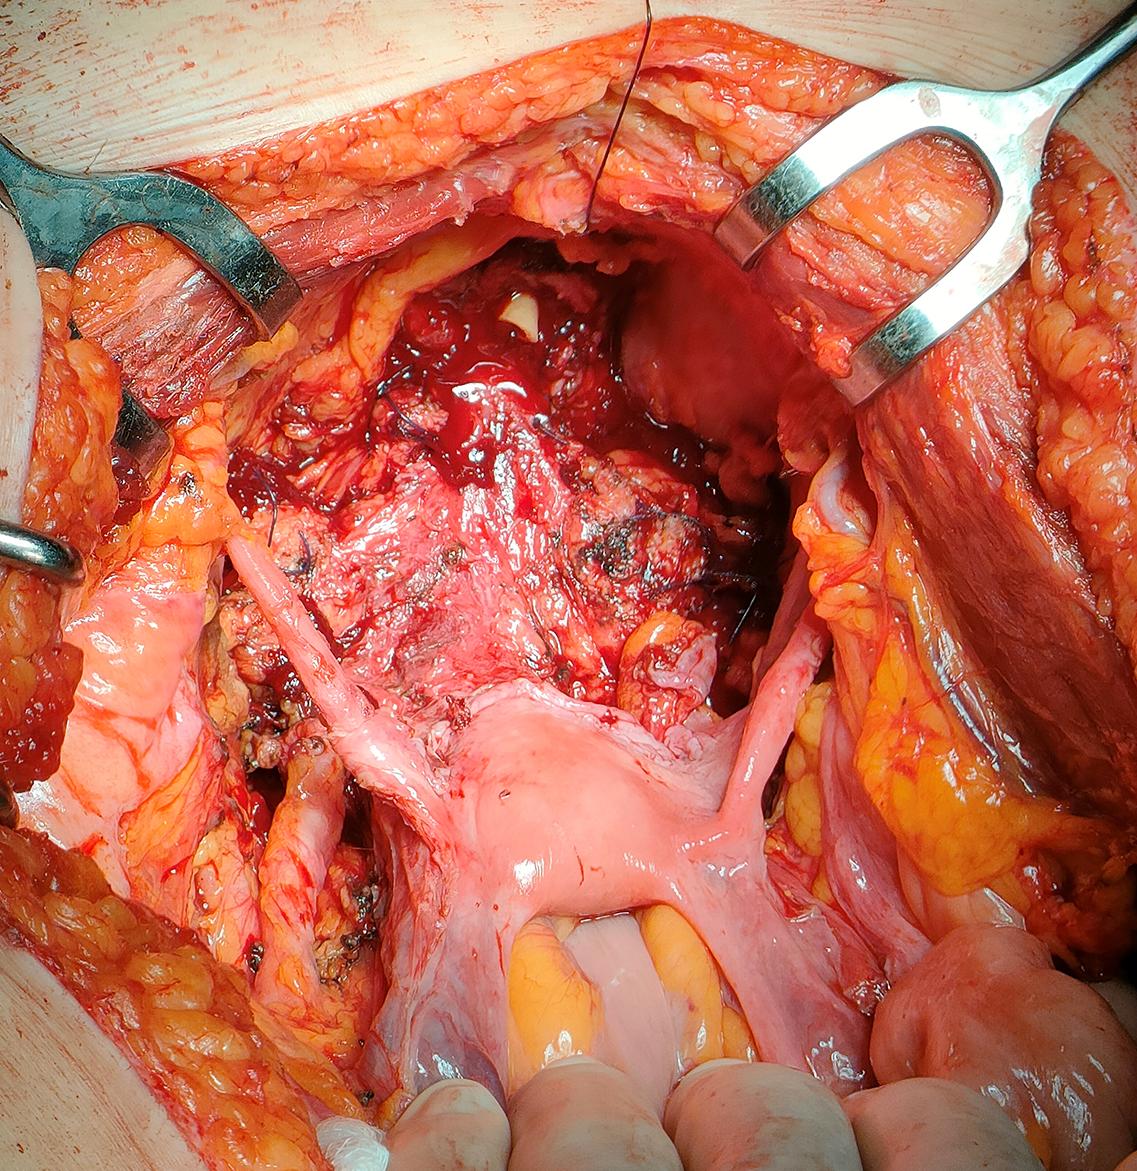

Surgical open technique

Patients were placed in the Trendelenburg supine position with pelvic hyperextension An incision was made on the midline from the pubis to the umbilicus, after dividing the muscular-aponeurotic planes, the peritoneal sac was opened Lysis of any bowel-omental adhesions was performed, and the bowel was cranially dislocated to expose the pelvis The bladder was then mobilized to the lateral walls of the pelvis The residual urachus was circumscribed – paying attention not to injure the lower epigastric vessels –, to be removed with the entire bladder A careful and systematic examination was carried out to determine the extent of the disease and the possible presence of metastases or massive retroperitoneal lymphadenopathy At this point the bowel was mobilized from the ascending colon, which was moved medially to gain access to the right ureter The mesentery was reversed until the retroperitoneal part of the duodenum was exposed The left colon and sigmoid were then mobilized to the inferior pole of the left kidney to give access to the left ureter The ureters were then isolated at their entrance to the bladder, were they were ligated and dissected To exclude neoplastic involvement, the distal margin was sent for extemporaneous histopathology The umbilical, uterine, superior, and inferior bladder arteries were carefully dissected bilaterally The bladder was mobilized and the junction between the cervix and the anterior wall of the vagina was identified along the anterior wall of the uterus The vaginal wall was then dissected at the level of the anteroventral plane of the vagina, at 2 o'clock and 10 o'clock, as close as possible to the bladder wall, in order to preserve the paravaginal tissues con-

taining the autonomic nerves that reach the proximal sphincter The superior and inferior bladder arteries were dissected at their origin, at the level of the hypogastric arteries, while the uterine arteries and vaginal branches to the paravaginal tissues were spared Once the retropubic space was created and opened, the endopelvic fascia was incised very close to the bladder neck to reduce the risk of inadvertent injury to the paraurethral neurovascular structures, which are crucial for sexual function and continence (Figures 1, 2) The urethra was carefully prepared, exposed and divided, and a specimen was sent for extemporaneous histopathological examination (Figure 3) At this time, careful dissection of the retroperitoneal lymph nodes was performed The margins of the resection were cranially defined by the common iliac artery,

Cisternino, L Capone, A Rosati, C Latiano, N Sebastio, A Colella, G Cretì Figure 1. Development of the plane between uterus and bladder Figure 2. Genital sparing cystectomy with sparing of the uterus, ovaries, tubes and vagina